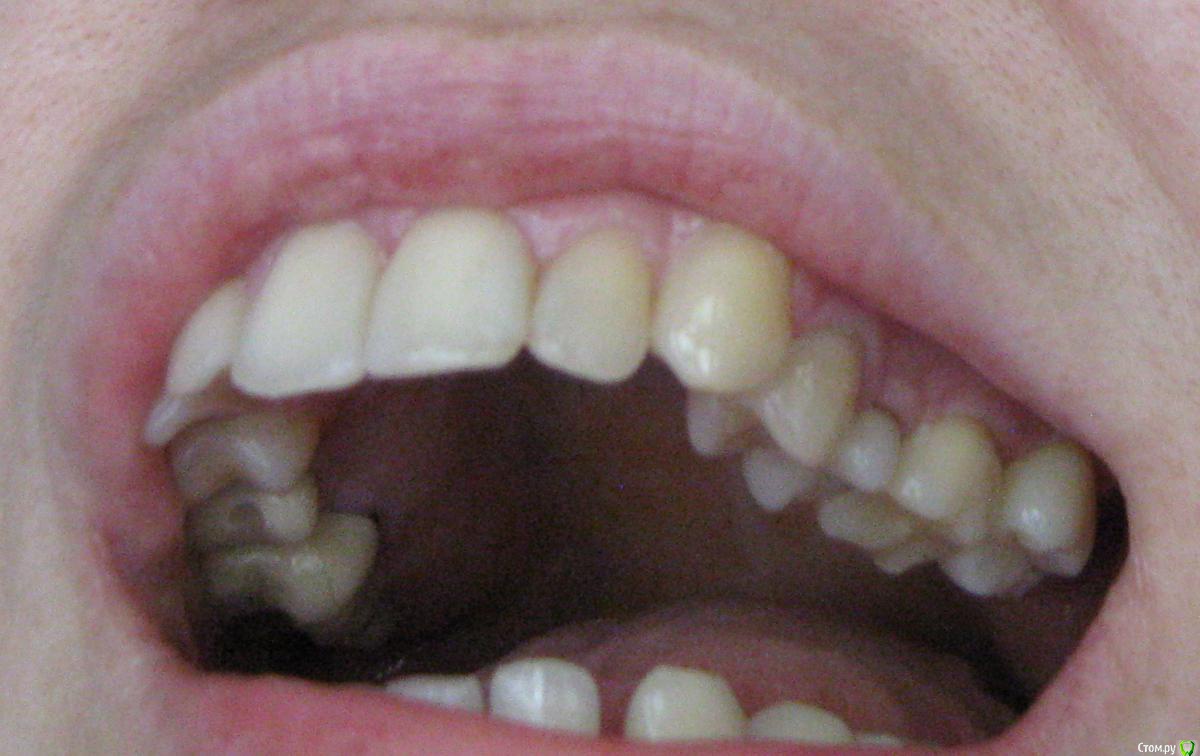

Miramar Опубликовано 30 июня, 2019 Автор Поделиться Опубликовано 30 июня, 2019 Вот фото по проблеме травмирования щеки (как смогла). Повторюсь: пока была восьмёрка, проблем с щекой не было; сейчас щека залазит под зуб, как только начинаю закрывать рот. Возможно, травмирует не только семёрка, но и шестёрка, т. к. под ней тоже ранки. Ссылка на комментарий